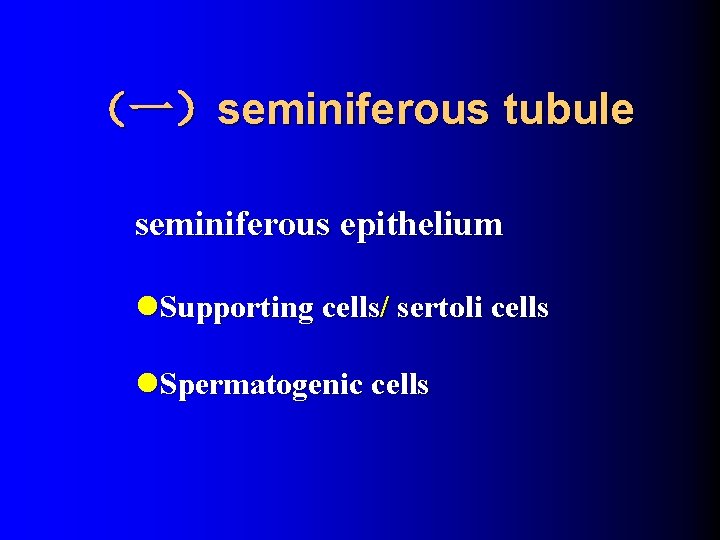

(一)seminiferous tubule seminiferous epithelium l. Supporting cells/ sertoli cells l. Spermatogenic cells